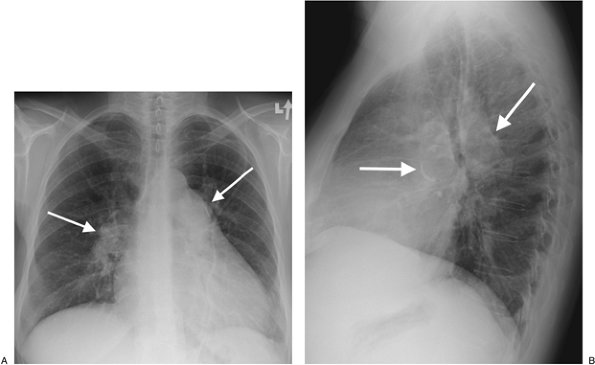

FIGURE 17-26. Primary pulmonary arterial hypertension. PA (A) and lateral (B) chest radiographs of a 54-year-old woman, obtained as part of a workup for lung transplantation, show enlargement of the central pulmonary arteries and narrowing of the peripheral branches. Fine curvilinear calcification can be seen outlining the central pulmonary arteries on the lateral view (arrowheads). There is also enlargement of the right atrium and right ventricle (note increased opacity posterior to the sternum on the lateral view).

PAH is defined as pulmonary artery pressures above the normal systolic value of 30 mm Hg or above the mean value of 18 mm Hg. There are numerous causes of PAH (Table 17-2), which is classically categorized as either precapillary or postcapillary. Regardless of the etiology, the radiologic features are similar and include enlargement of the central pulmonary arteries and narrowing or "pruning" of the peripheral pulmonary artery branches (Fig. 17-26). Right ventricular enlargement is often appreciated on the lateral chest radiograph. However,

substantial PAH may be present in patients with normal chest radiographs. CT more accurately depicts the size of the pulmonary arteries and cardiac chambers. As a general rule, PAH is present when the main pulmonary artery diameter exceeds that of the ascending aorta or is 29 mm or more in diameter (15) (Fig. 17-27). In long-standing and severe PAH, the enlarged central pulmonary arteries may develop thrombus and peripheral calcification. This is most often seen in patients with Eisenmenger physiology, a condition characterized by a reversal in the direction of a long-standing severe left-to-right shunt (i.e., atrial septal defect, ventricular septal defect, patent ductus arteriosus) (Fig. 17-28). In postcapillary and some precapillary disorders, changes of pulmonary venous hypertension may be seen. The most salient finding is cephalization of pulmonary vasculature, which represents recruitment of upper lobe vasculature secondary to a diversion of blood flow. Pericardial effusions, usually small to moderate in size, are commonly associated with PAH.